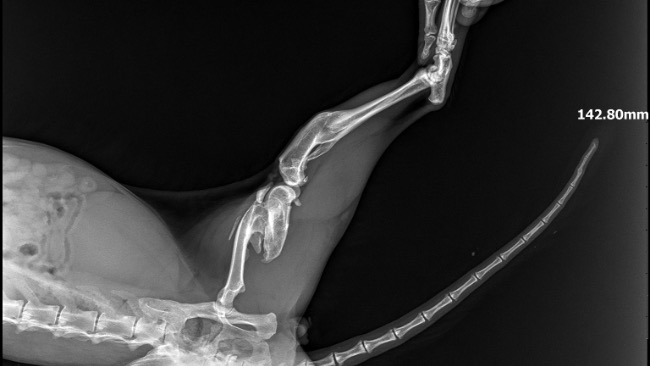

Na pewno większość z was zna historię tej dwójki. Od wielu tygodni zgłoszenia do różnych organizacji, nikt nie pomógł. Dostaliśmy to zgłoszenie 26.08- dwa zaniedbane, koty przy bardzo ruchliwej ulicy Mazowieckiej- żyły w bramie dokarmiane przez mieszkańców. Jeden kotek w złym stanie. Niezwłocznie udaliśmy się na miejsce. Akcja okazała się trudniejsza niż myśleliśmy… wysoka zamknięta brama, ciężka do przejścia, oraz bardzo nieufne koty, uciekające od klatek. Jedną kotkę udało się złapać po kilku dniach. Trafiła do lecznicy, wykonaliśmy diagnostykę, przeszła zabieg stomatologiczny usunięcia połamanych zębów. Z kotkiem w złym stanie było ciężko, omijał wszystko. Udało się go złapać dopiero 30.09 po wielu godzinach łapanki. To kastrowany kocurek. Niestety faktycznie jego stan jest bardzo zły. Wykonaliśmy szereg badań- Rtg stare złamanie kości udowej, USG- powiększone, zatarte nerki, badanie krwi niestety potwierdziło przewlekłą niewydolność nerek. Wyniki są bardzo złe, a rokowania ostrożne. Na nieszczęście ma też połamane zęby, które pogarszają sprawę, te w najgorszym stanie zostały usunięte. Jeśli uda się poprawić parametry nerkowe, przejdzie pełny zabieg stomatologiczny. Ma też świerzbowca usznego, oraz wielki kamień woszczynowy w uchu, zatykający praktycznie kanał słuchowy (który został usunięty) Jest źle… Ale walczymy, łatwo się nie poddamy. Szkoda tylko że szybciej do nas nie trafił, pewnie rokowania byłyby lepsze. Nasza sytuacja finansowa jest fatalna. Mamy kilkanaście tysięcy długu w różnych lecznicach. Musieliśmy wstrzymać przyjmowanie kolejnych kotów (a rzadko odmawiamy pomocy) Mamy pod opieką około 40 kotów, wiele z nich chore, wymagające zabiegów i diagnostyki. Jeśli nie uda nam się zebrać pieniędzy i załatać dziur, nie będziemy mogli dalej pomagać. Chore zwierzaki nie mogą czekać na „lepsze czasy”- pomożecie ?